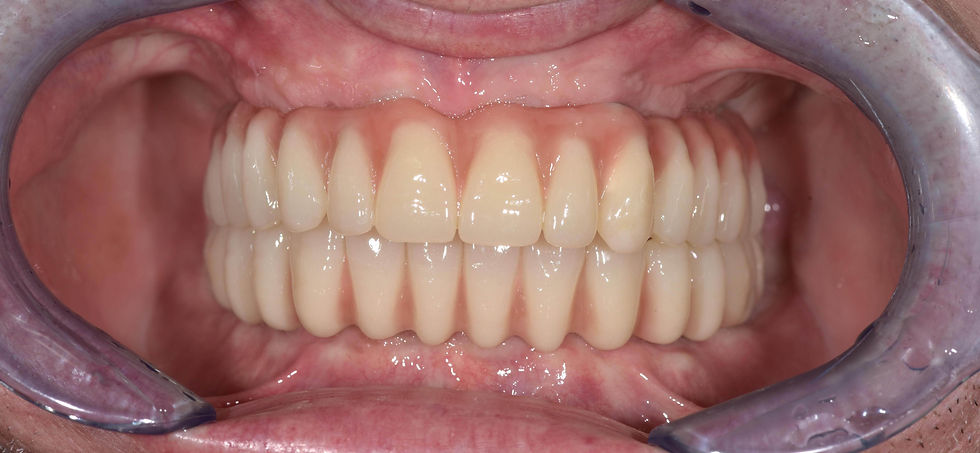

Final aspect of the rehabilitation.

Image courtesy of: Dr. Costantino Vignato, Dr. Giuseppe Vignato